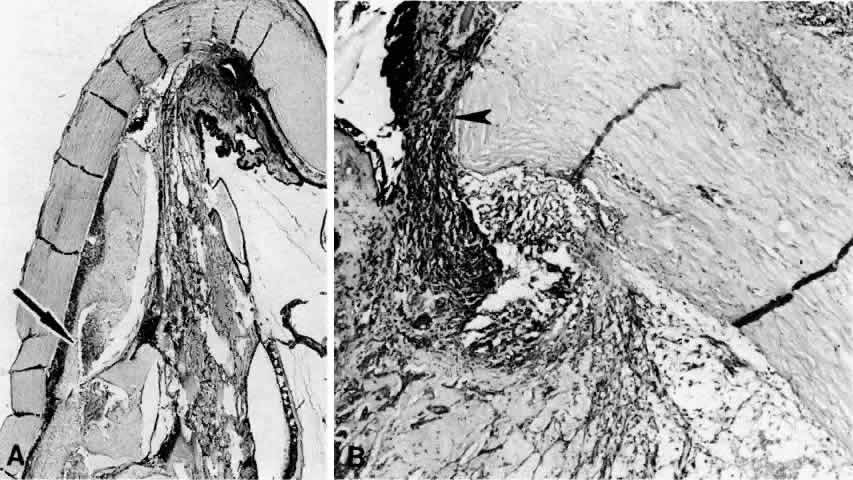

A subconjunctival abscess,72 orbital pseudotumor,73 episcleritis,74–76 scleritis (Fig. 14),9,19,20,65,68,77,78 and vasculitides (Figs. 15 and 16)79–81 such as Wegener's granulomatosis79 (see Fig. 16), polyarteritis nodosa,80,81 occlusive vasculitis,65 or nonspecific vasculitis (see Fig. 15) can produce suprachoroidal edema even without overt signs of inflammation. Scleritis, however, may sometimes produce choroidal inflammation with secondary vasodilation and serous effusion into the suprachoroidal and subretinal space. An infected scleral buckle may also produce a ciliochoroidal effusion months to years after its placement. Removal of sutures and all implanted material is necessary to promote resolution of the effusion.

Fig. 14. Extensive ciliochoroidal effusion (asterisk) associated with a zonular granulomatous inflammatory infiltration in the episclera (arrowheads) of the eye of a 78-year-old man with rheumatoid arthritis.68 Diffuse, nodular inflammatory infiltrates are present in the markedly edematous ciliary body and choroid. There are several folds of retinal pigment epithelium and inner layers of choroid (arrows) and a flat serous detachment of the retina (H & E, × 40).

Fig. 15. A spontaneous ciliochoroidal effusion was mistaken for a malignant melanoma in a 61-year-old woman who presented with pain, blurred vision, keratitic precipitates, and aqueous cells and flare. A. Gross appearance of the ciliochoroidal effusion (large arrowheads). Small whitish inflammatory nodules are present in the choroid (small arrowheads). The apparent retinal detachment is artifact. B. An extensive ciliochoroidal effusion (asterisk) with a moderately intense chronic inflammatory cellular infiltration. (H & E, × 20). C. The choroid viewed posteriorly, showing occlusive granulomatous vasculitis (arrow) and an intense lymphocytic infiltration crowding the choriocapillaris. The retinal pigment epithelium is intact (H & E, × 290). D. Intense lymphocytic infiltration of choroid, inner scleral lamellae, and episclera (H & E, × 55). E. Diffuse scleritis viewed posteriorly, showing perineural lymphocytic infiltration in the episclera and within a scleral canal (arrowheads) (H & E, × 55).

Fig. 16. Peripheral marginal corneal degeneration and conjunctival ulceration developed in a 61-year-old woman with Wegener's granulomatosis.79 Ciliochoroidal effusion (asterisks) was not a clinical problem, but was found on autopsy examination in association with an occlusive vasculitis with fibrinoid necrosis of the anterior and long ciliary arteries. Intense episcleritis is evident (arrow) (H & E, × 55).